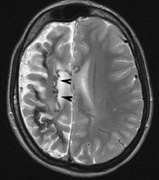

Fig. 15. Tuberous Sclerosis Complex. (a) Patient 1: Axial CT scans demonstrating typical calcification of subependymal nodules in a 13-year-old girl with a history of seizures. (b and c) Patient 2. (b) Axial T2-weighted images demonstrate calcified subependymal nodules (arrowheads) and cortical tubers typical of tuberous sclerosis. (c) Widespread cortical tubers are seen on a coronal FLAIR sequence as thickening of the cortex and high signal of the subcortical white matter.